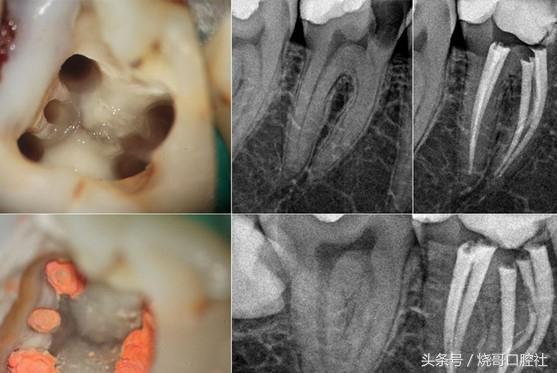

Une dent cariée avec une cavité à l'intérieur indique que les bactéries ont envahi la pulpe et qu'il y a eu endodontie ou nécrose complète de la pulpe.

1) S'il n'y a qu'un défaut, vous pouvez simplement le combler en meulant le matériau décomposé et en le remplissant (obturation).

2) Si les bactéries ont infecté la pulpe, un traitement de canal, c'est-à-dire l'extraction du nerf, suivie d'une obturation et de la pose d'une couronne, est nécessaire.

3) Enfin, si la pulpe est complètement nécrosée et infectée par les tissus périapicaux, un traitement du canal radiculaire est également nécessaire, et les cas graves peuvent nécessiter une extraction.

Lorsqu'une dent est pourrie, il faut l'obturer rapidement en retirant les tissus malades à l'aide d'instruments professionnels et en choisissant le matériau approprié pour obturer la dent de manière étanche afin d'éviter que les bactéries ne se développent dans les couches plus profondes. Si le nerf de la dent n'est pas atteint, la dent peut être obturée en une seule séance. Si le nerf de la dent est atteint, la dent devra être traitée à plusieurs reprises par un traitement de canal.

Bonjour, la carie dentaire pourrit le vide, ce qui indique une pulpite grave, cette fois il faut faire des plombages, un traitement de canal, sinon cela affectera la santé des dents voisines, et finalement conduira à la perte de toutes les dents, l'examen et le traitement en temps opportun à l'hôpital dentaire professionnel est la clé.